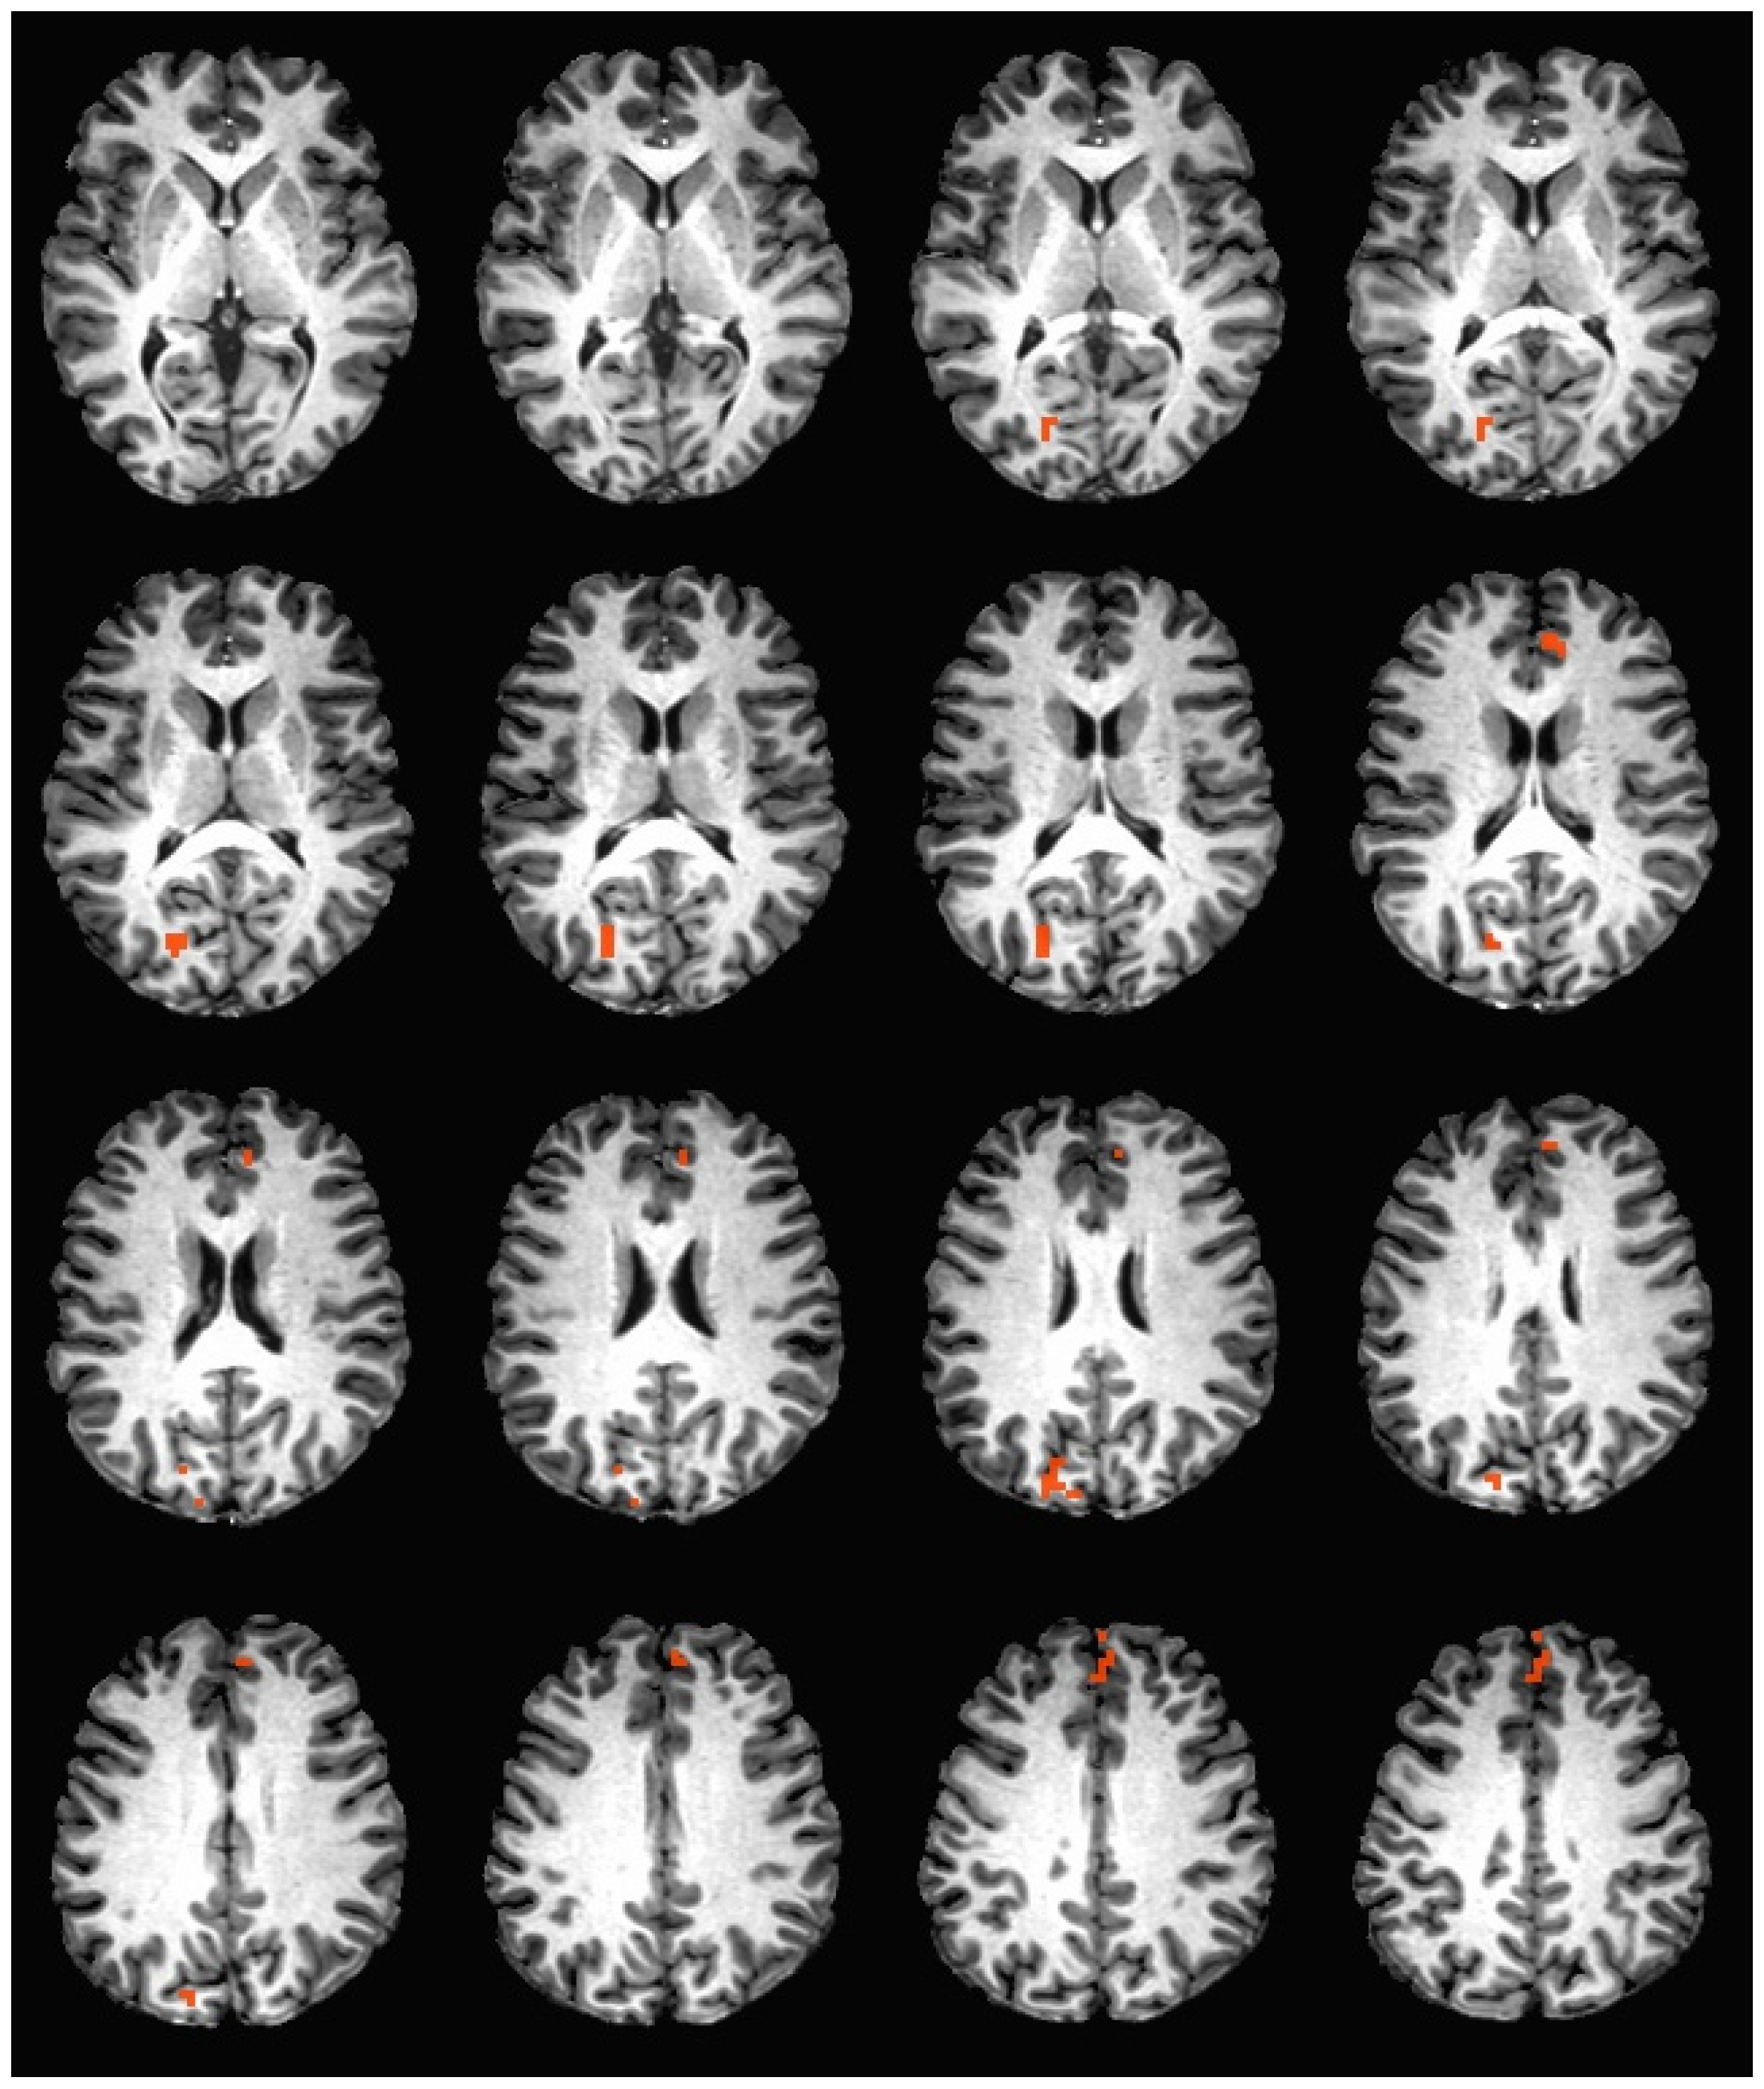

During the hedonic evaluation of sucrose, caffeine non-consumers had significantly greater neuronal activation in the anterior cingulate, medial frontal gyrus, right superior frontal gyrus, OFC BA 10, posterior cingulate, cingulate gyrus, and precuneus (See Table 6 and Figure 4).

Figure 4. Brain activation during the hedonic evaluation of sucrose. Orange indicates areas where caffeine non-consumers had significantly greater activation in comparison to caffeine consumers.

During the hedonic evaluation of sucrose, caffeine non-consumers demonstrated significantly greater activation in both hemispheres of OFC BA 10, an area associated with encoding the incentive value of a stimulus during a decision-making task [37,38,39]. The OFC has been activated in response to abstract internal goals, such as rewards and punishments, while other tasks are being performed [37,38,39]. The OFC has been reported to be responsive to the reward value of tastes, as it associates other stimuli with tastes to produce representations of expected reward value [37,40]. A reward stimulus has been found to induce increased activation in OFC BA 10 when already activated by working memory processing [41]. Further, the OFC is activated by monetary rewards and punishment, with more activation reported following a punishment outcome [38].

During the hedonic evaluation of caffeine and sucrose, activation in the anterior cingulate cortex (ACC) was significantly greater in caffeine non-consumers. During the hedonic evaluation of caffeine, only activation in the left anterior cingulate cortex was found to be significantly greater in caffeine non-consumers in comparison to caffeine consumers. Lateralization in the ACC has been found during error processing and conflict monitoring, where correct inhibitions only occurred in the right ACC [42]. Further, observational fear learning has been found to only be activated in the right, but not the left ACC [43]. The distinction that right ACC activation only occurred during the hedonic evaluation of sucrose and not during the hedonic evaluation of caffeine suggests that sucrose may have been a more intense experience for caffeine non-consumers. Psychophysical data supports this assertion, as caffeine non-consumers provided significantly higher intensity ratings for sucrose post-scan when compared to caffeine consumers (Table 3).

Overall, the ACC has been associated with an overall neural circuit that uses past action-reward history to learn action value in order to guide voluntary choice behavior [44]. This process requires referencing a history of outcomes regarding a given choice [44]. Further, previous studies suggest that reward processing in the ACC may also guide choice behavior, as it relates actions to their consequences [45]. This suggests that ACC has an essential role in learning and using extended action-outcome histories to make voluntary choices.

It is important to emphasize that activity in the OFC is representative not merely of a reward per se, but of a detailed and information rich representation of reward [46]. Similarly, the ACC references past-action reward history and is not a direct reflection of the reward value [44,45]. Therefore, the results are not necessarily indicative of caffeine non-consumers finding tastes to be more or less rewarding than caffeine consumers. A more plausible explanation may be that greater activation in the OFC and ACC found in caffeine non-consumers suggests a greater cognitive expenditure to use past reward history and process the representation of a reward, in order to make a voluntary choice, which in this case, was the hedonic rating.

During the evaluation of sucrose, caffeine non-consumers also demonstrated greater activation in both the left and right of the posterior cingulate and cingulate gyrus. The posterior cingulate cortex has been associated with memory retrieval, namely autobiographical memory retrieval [50]. The posterior cingulate cortex also subserves evaluative functions such as monitoring sensory events and behavioral actions in the service of spatial orientation and memory [51].